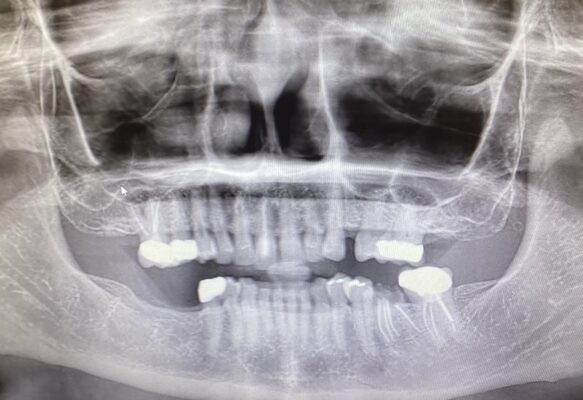

Patient wants #12 and #19 replaced with implants.

I was going to try to increase her VDO using a partial for #19. Would you replace #13/14 to gain more space as well? How would you approach this case?

• Without having a lot of information and just taking a look at that cast tge plan on number 12 seems to have plenty of space the concern I’m sure for you is number 19. I would extract and graft number 18 and then number 14, potentially 13 and 14 could have crowns to open up more restorative space and you can even do some alveoplasty on 19 prior to placing the implant and place the implant deeper so you have plenty of restorative space. You could do all of those or just some of those as needed, which would be pretty straightforward.

• One of the cardinal rules for implants IMO is to establish stable posterior occlusion. We’re already missing most of the molars on the lower arch. I think that seems like a good place to try to establish a good foundation.

The contralateral side is missing the posterior stops as well.

I think mounting the case on an articulator, and redesigning the case with stable stops on the mandibular arch. Can 19 and 30 be implant sites? You might need to open up the patient’s occlusion to make it happen.

For sure the opposing teeth would need to be reviewed. Do you have a pano? If some upper teeth are extracted to facilitate space, we’d need to see bone height availability.

• @ivan-chicchon thank you everyone for the feedback. It is extremely helpful. I added the pano